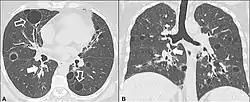

Left lung completely affected by bullae shown in contrast to a normal lung on the right.

In the lungs, emphysema involves enlargement of the distal airspaces,[2] and is a major feature of chronic obstructive pulmonary disease (COPD). Other pneumatoses in the lungs are focal (localized) blebs and bullae, pulmonary cysts and cavities.